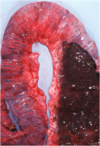

Q

This is a picture of a rumen. What lesion is shown here?

A

Acute, multifocal to coalescing ulcerative ruminitis